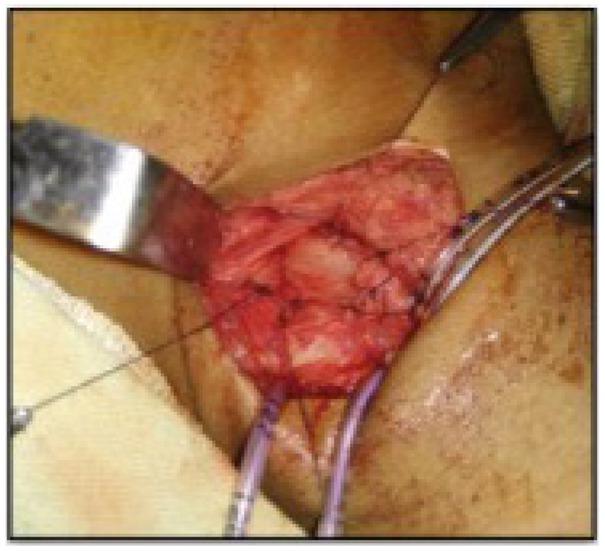

Figure 4